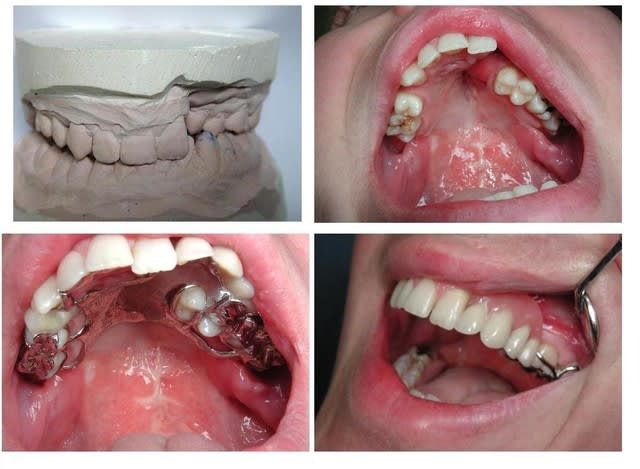

La réhabilitation prothétique et esthétique d’un patient présentant une FLP requiert de la part du prat comme du proto une symbiose, des acquis et une collaboration pour mener à bien les souhaits de ces patients, retrouver le sourire et la satisfaction au cœur de la famille et de la société.

Les avances technologiques et scientifiques dans la restauration de ces malfaçons sont indéniables, les efforts et la bonne volonté ne suffisent pas, trajet long et pénible de ces patients et parents pour aller au bout de ces interventions, lourdes et pénibles.

La réhabilitation de l’équilibre fonctionnel et esthétique par une PPAM est difficile et la doc sur le sujet rare.

Juste 2 cas que donnent l’ampleur de l’élaboration de prothèses atypique, pour le bien être des patients concernés.

Et de 1

Et de 2

joli, ou plutot jolie

c'est beau le sourire retrouvé (trouvé?)d'une jeune fille

Meme impression que toi, athos; ce sourire est le V de ta victoire, rick. Cela n'a pas du etre facile. Beau succes.